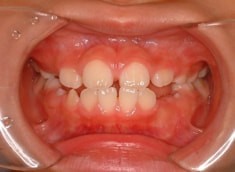

小児期ケース:反対咬合(受け口)

治療前